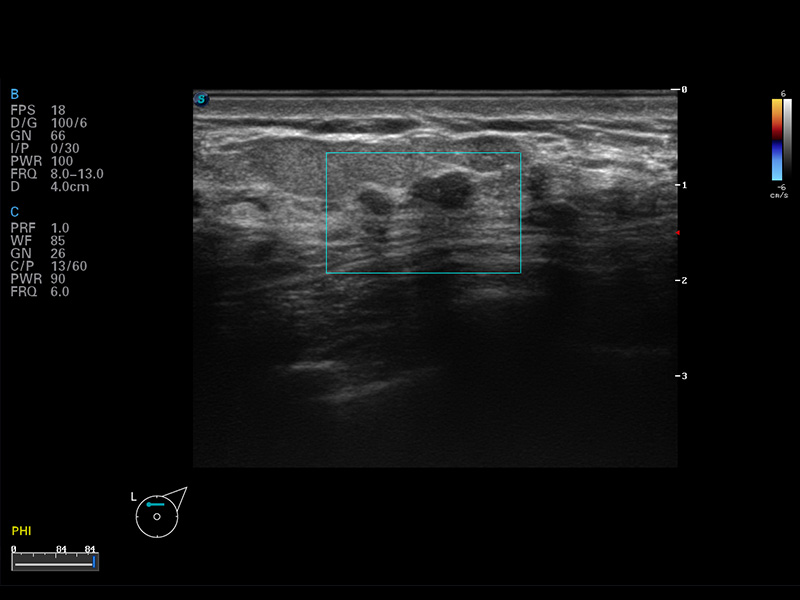

S8 EXP便携式彩色多普勒超声诊断仪是九州酷游研发的高端全身应用型便携彩超。高通道的VIS平台融合可视化(Visual)、智能化(Intelligent)和人性化(Smart)的特点,配以九州酷游自主研发生产的探头大家族,使您能够快速、准确的获得病人信息,提高工作效率的同时减轻疲劳。

成像技术

多波束形成器

μ-Scan微米成像

谐波成像

实时宽景成像

空间复合成像

3D/4D成像